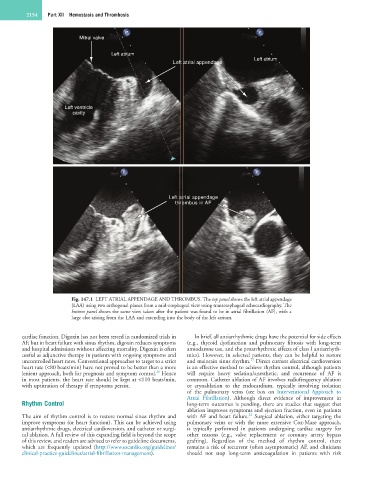

Fig. 147.1 LEFT ATRIAL APPENDAGE AND THROMBUS. The top panel shows the left atrial appendage

(LAA) using two orthogonal planes from a mid-esophageal view using transesophageal echocardiography. The

bottom panel shows the same view taken after the patient was found to be in atrial fibrillation (AF), with a

large clot arising from the LAA and extending into the body of the left atrium.